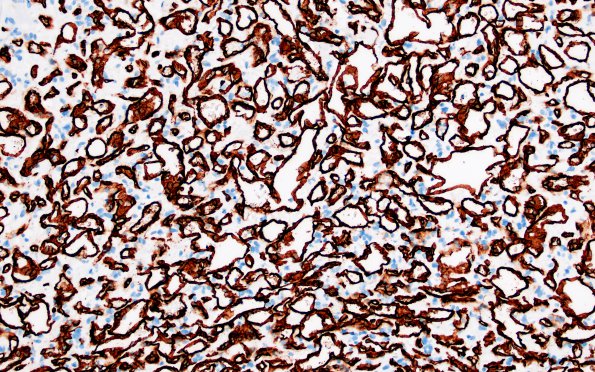

11B2 Hemangioblastoma (Case 11) CD34 20X

Marked vascularity of the tumor is shown (CD34 IHC)